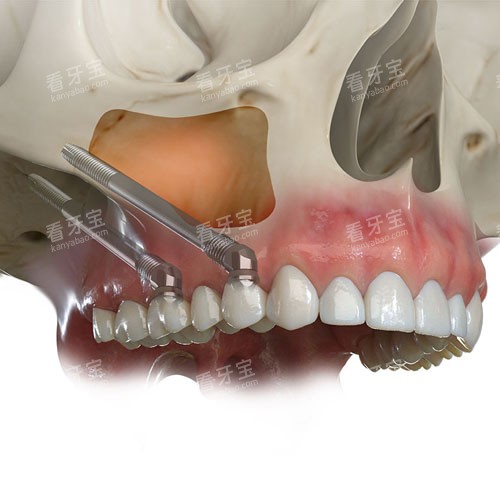

穿颧种植牙是一种将种植体穿过上颌窦底或颧骨区域,直接固定于颧骨或上颌骨的种植修复技术。与传统种植体仅植入牙槽骨不同,其核心在于利用颧骨这一人体较坚硬的骨骼(密度约为皮质骨的2倍),为种植体提供稳定的力学支撑。

利用正规软件(如Simplant、NobelClinician)模拟种植体植入角度、深度及长度。例如,对于上颌窦前壁薄弱的患者,软件可自动调整种植体倾斜角度,避开窦腔;对于颧骨较薄的区域,可选择短种植体或双颧种植方案。

?上颌窦穿透:用超声骨刀轻柔分离窦底黏膜,避免穿孔;

?颧骨定位:通过导板引导,确保种植体与颧骨长轴呈30°-45°夹角,以获得较佳应力分布。

(3)种植体植入